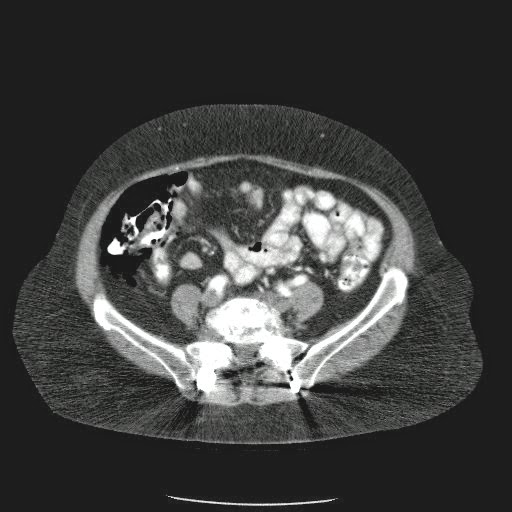

Caso Interesante #4

Adulto masculino, 1 semana de fiebre y malestar general.

¿Dónde esta ubicado el hallazgo?